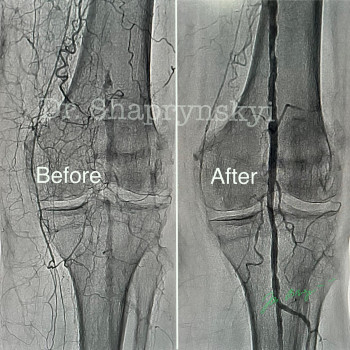

Обладаю высшей квалификационной категорией и 17-летним опытом работы в области сосудистой хирургии. Моя клиническая практика тесно связана с научной деятельностью, результатом которой стала защита 10 патентов на полезные модели и новейшие способы лечения сосудистых патологий. Использование авторских разработок и многолетнего стажа позволяет мне внедрять наиболее эффективные и безопасные решения для здоровья моих пациентов.